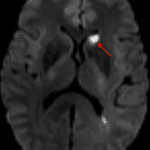

- Hypodensity in the left caudate head

- Acute left caudate head infarct

Age-indeterminate left caudate head infarct, which can also be further evaluated with MRI.